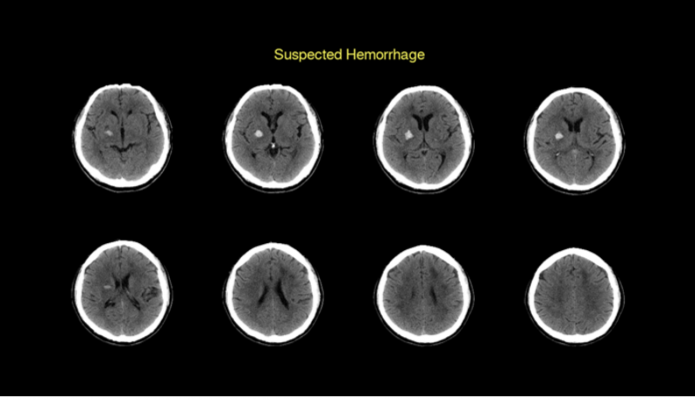

In 2019, RapidAI introduced Rapid ICH, the next step in artificial intelligence (AI)-powered imaging technology for hemorrhages. Now with the acquisition of EndoVantage, the company will also add a concentration on aneurysm. Started at Mayo Clinic and Arizona State University, EndoVantage has developed a powerful award-winning computational platform that provides comprehensive cerebral aneurysm management, automating the entire workflow from initial assessment, growth monitoring, to treatment planning. It utilizes CTA and MRA scans to deliver results that help physicians find and track aneurysm progression, and leverages data from 3-D rotational angiograms to deliver detailed 3-D models of a patient’s vasculature and allow presurgical planning for the repair of the aneurysm.